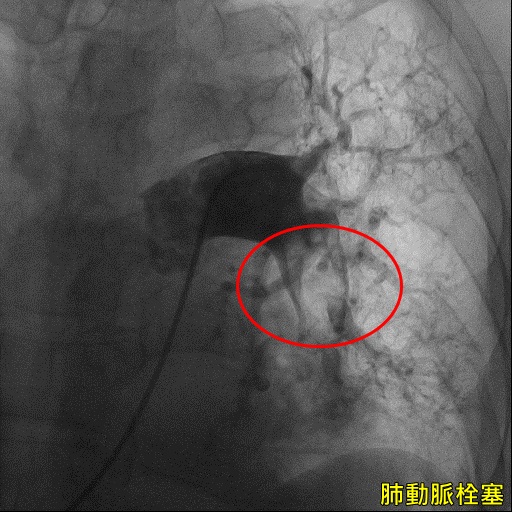

▲ 心導管影像可看出肺動脈栓塞。(圖/亞大醫院提供)

亞洲大學附屬醫院心臟檢查室主任張育晟表示,患者到院時血壓極低,檢查發現疑似肺動脈栓塞造成休克,進一步檢查發現雙側肺動脈出現大塊血栓,病情十分嚴重。